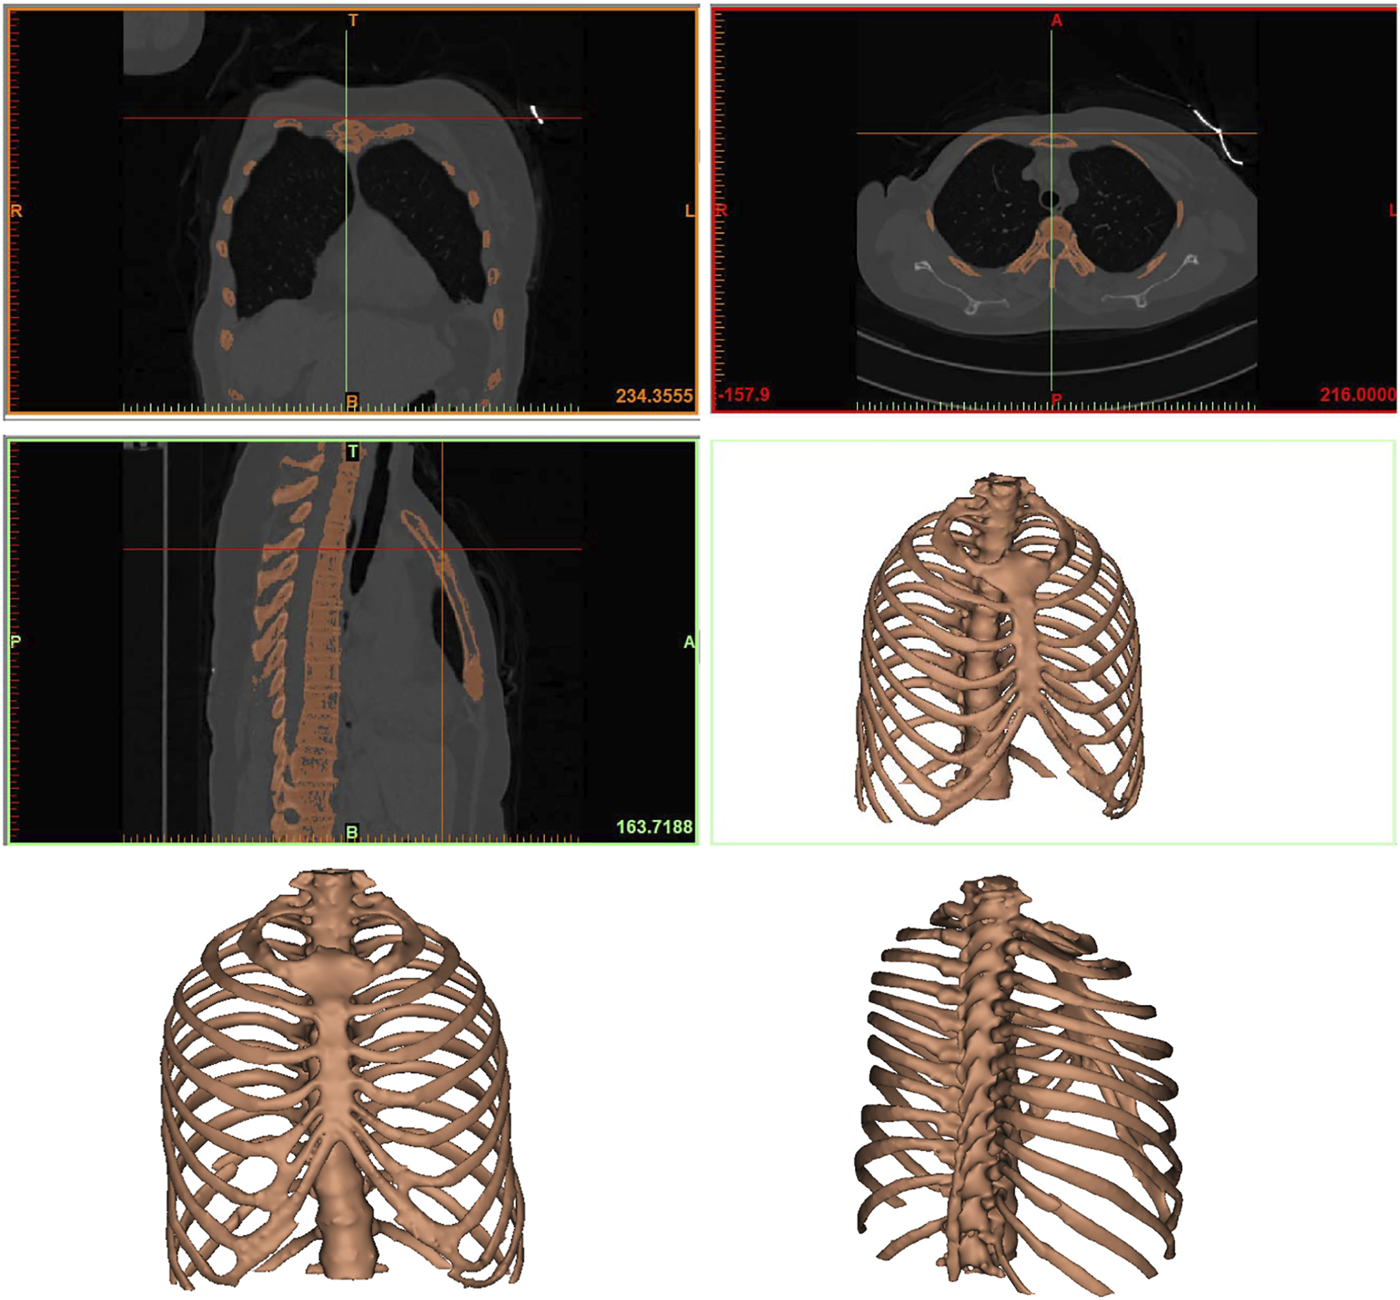

A patient with a rib fracture sustained in a car accident underwent a CT examination and modeling after admission. In order to better characterize the injured site of the patient, Mimics software was used to reconstruct the thoracic rib model according to the CT data (Figure 1). A common fracture of the sixth rib was taken as an example to analyze the force of the anterior, lateral and posterior ribs fixed by absorbable plates and screws. Therefore, this part of the study involves construction of a computer finite element model that takes into account the geometry of ribs and plates, material properties and boundary conditions, as well as the respiratory muscle forces.

FIGURE 1

The finite element model of the rib. Anteroposterior and lateral thoracic models were reconstructed from CT data.